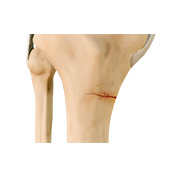

Fractures of the Tibia

The lower leg is made up of two long bones called the tibia and fibula that extend between the knee and ankle. The tibia or shinbone is the larger of the two bones. It bears most of the body’s weight and helps form the ankle joint and knee joint. A crack or break in the tibia is referred to as a tibial fracture. The tibia is the most frequently fractured long bone of the body. It normally takes a great amount of force for a fracture of the tibia to occur.

Stress Fracture of the Tibia

A stress fracture of the tibia or shinbone is a thin fracture, also called a hairline fracture that occurs in the tibia due to excess stress or overuse. The tibia is a weight-bearing bone in which stresses can accumulate from activities such as running and jumping.